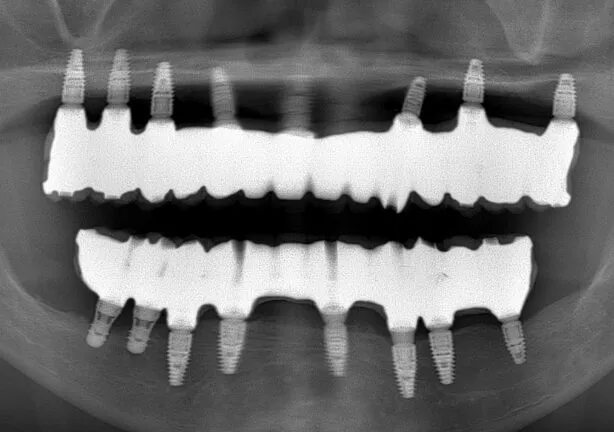

case1

After

治療内容 | 口腔内診査〜カウンセリング 歯周初期治療 仮の義歯にて噛む位置の再設定 インプラント埋入 仮歯にてインプラントを含めた噛む位置の決定 最終的な被せ物(ジルコニア)の型取り〜装着 |

治療期間 | 3年 |

治療回数 | 100回 |

リスク | 手術、並びに治療における疼痛 今後のメンテナンスが必須となる |

費用(税込) | 約¥11,000,000 |